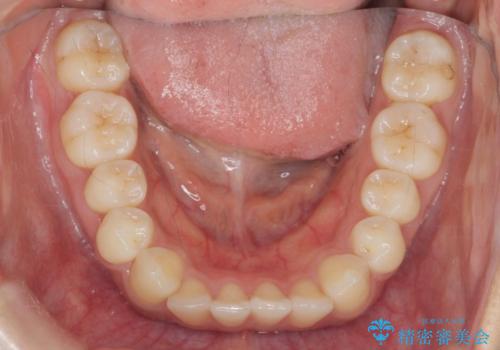

前歯のねじれ、すれ違いを改善 部分ワイヤー+マウスピース矯正

- 上下前歯のすれ違い、ねじれのある歯並びの矯正治療を求めて来院されました。

前歯のすれ違いが改善することで噛みやすくなった。と矯正治療の結果に満足いただくことができました。